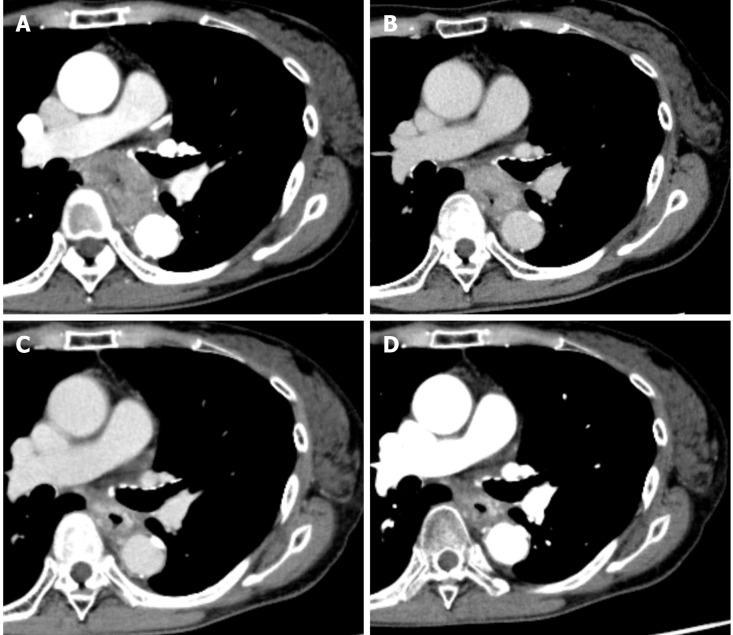

We report a successful case of a 59-year-old female with unresectable locally advanced T4 ESCC treated by two additional courses of chemotherapy with CF after induction chemotherapy with docetaxel, cisplatin and fluorouracil (DCF) followed by dCRT. Initial esophagogastroduodenoscopy (EGD) detected a type 2 advanced lesion located on the middle part of the esophagus, with stenosis. Computed tomography detected the primary tumor with suspected invasion of the left bronchus and 90° of direct contact with the aorta, and upper mediastinal lymph node metastasis. Pathological findings from biopsy revealed squamous cell carcinoma. We initially performed induction chemotherapy using three courses of DCF, but the lesion was still evaluated unresectable after DCF chemotherapy. Therefore, we subsequently performed dCRT treatment (CF and radiation). After dCRT, prominent reduction of the primary tumor was recognized but a residual tumor with ulceration was detected by EGD. Since the patient had some surgical risk, we performed two additional courses of CF and achieved a clinically complete response. After 14 mo from last administration of CF chemotherapy, recurrence has not been detected by computed tomography and EGD, and biopsy from the scar formation has revealed no cancer cells.

我们报告了1例成功治疗的病例,患者为59岁女性,患有不可切除的局部晚期T4期ESCC,在接受多西他赛、顺铂和氟尿嘧啶(DCF)诱导化疗后,再接受两周期CF化疗,随后进行同步放化疗。最初的食管胃十二指肠镜检查(EGD)发现食管中段有一处2型进展期病变并伴有狭窄。计算机断层扫描发现原发性肿瘤,怀疑侵犯左支气管,与主动脉直接接触90°,并有上纵隔淋巴结转移。活检病理结果显示为鳞状细胞癌。我们最初采用三周期DCF进行诱导化疗,但DCF化疗后病变仍被评估为不可切除。因此,我们随后进行了同步放化疗(CF和放疗)。同步放化疗后,原发性肿瘤明显缩小,但EGD检查发现有残留肿瘤伴溃疡形成。由于患者存在一定的手术风险,我们又进行了两周期CF化疗,实现了临床完全缓解。在最后一次CF化疗后14个月,计算机断层扫描和EGD检查未发现复发,瘢痕形成部位的活检未发现癌细胞。